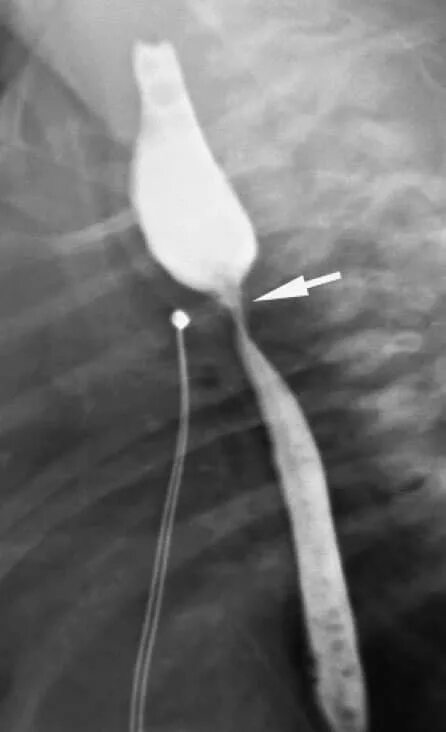

Стеноз пищевода симптомы